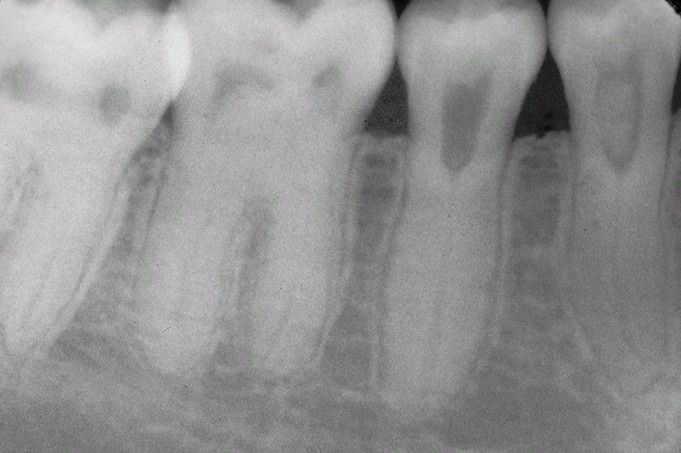

Dentin Dysplasia Type II (DD-II).

Radiographic appearance of the permanent dentition exhibiting thistle tube–shaped enlargements of the pulp chambers and numerous pulp stone